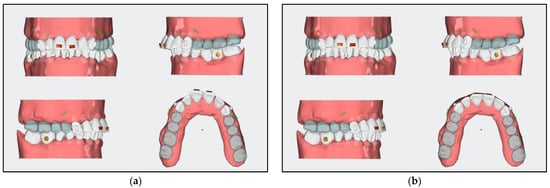

3.1. Case No. 1

- For aligner stages 1 to 16, a mini screw in the area between teeth 34 and 36 was added for the distalization and uprighting of teeth 36 and 37.

- The distalization of teeth 16, 17, 26, and 27 was planned with aligners by adding Class II elastics of 6 Oz and a quarter of an inch.

- A horizontal attachment was added onto the temporary crown of tooth 21 for distalization using the implant as skeletal anchorage.

- After stage 16, rescanning should be carried out, and the space for the implant surgery of tooth 35 should be evaluated.